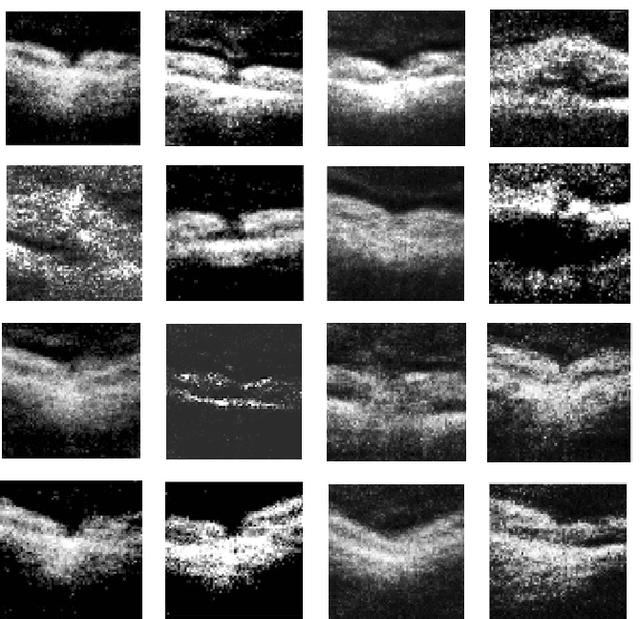

Abstract:We report, to our knowledge, the first end-to-end application of Generative Adversarial Networks (GANs) towards the synthesis of Optical Coherence Tomography (OCT) images of the retina. Generative models have gained recent attention for the increasingly realistic images they can synthesize, given a sampling of a data type. In this paper, we apply GANs to a sampling distribution of OCTs of the retina. We observe the synthesis of realistic OCT images depicting recognizable pathology such as macular holes, choroidal neovascular membranes, myopic degeneration, cystoid macular edema, and central serous retinopathy amongst others. This represents the first such report of its kind. Potential applications of this new technology include for surgical simulation, for treatment planning, for disease prognostication, and for accelerating the development of new drugs and surgical procedures to treat retinal disease.